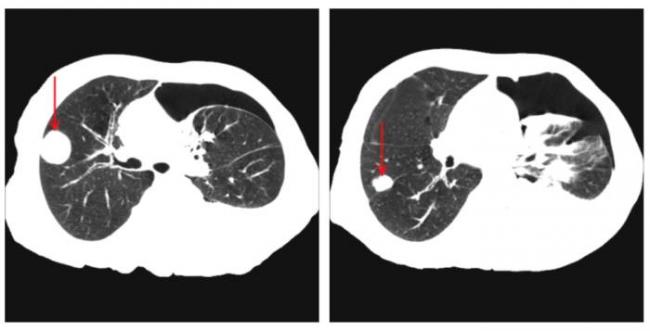

Как очаги в легких выглядят на снимке КТ?

Чтобы человек несведущий смог разобраться в результатах КТ, следует знать о нюансах чтения снимков. Рассмотрим самые актуальные:

- Очаговые образования представляют собой участки белого цвета на черном фоне (на снимке-негативе). В реальности пораженная область, скорее всего, имеет более темный цвет, чем здоровые ткани легкого.

- Если врач заметит на снимке участки кальцинирования или обызвествления (капсул, пропитанных солями кальция) вокруг очага, это может быть признаком доброкачественности образования. Кальцинаты по цвету похожи на кости скелета, видимые на этом снимке. Такие явления часто обнаруживаются после затяжных простудных заболеваний, бронхитов или уже излечененного туберкулеза и представляют собой некий шрам на легких. Пациента с образованием, на котором заметны признаки кальцината, пульмонологи обычно просят раз в полгода делать контрольные снимки.

- В случае, когда образование представляет собой так называемое «облачко» или очаг по типу «матового стекла», требуется более предметное обследование. Внешне оно выглядит как затуманенная область с размытыми границами. В ряде стран пациентам с такими образованиями сразу рекомендуется операция, даже если оно не растет. Уже доказано, что в 80% случаев такие очаги являются предраковым состоянием легких. Альтернатива немедленной операции — постоянное наблюдение с контрольными снимками раз в полгода-год.

Очаговые изменения

Очаговые изменения в лёгких могут быть разного размера. Очаги мелкого диаметра 1-10 мм выявляются при различных диффузных патологиях лёгочной ткани. Очаги с высокой плотностью и довольно чётки краями в основном наблюдаются в интерстиции лёгкого. Различные очаги низкой плотности, напоминающие матовое стекло, с нечёткими контурами возникают при патологических изменениях в респираторных отделах дыхательных органов.